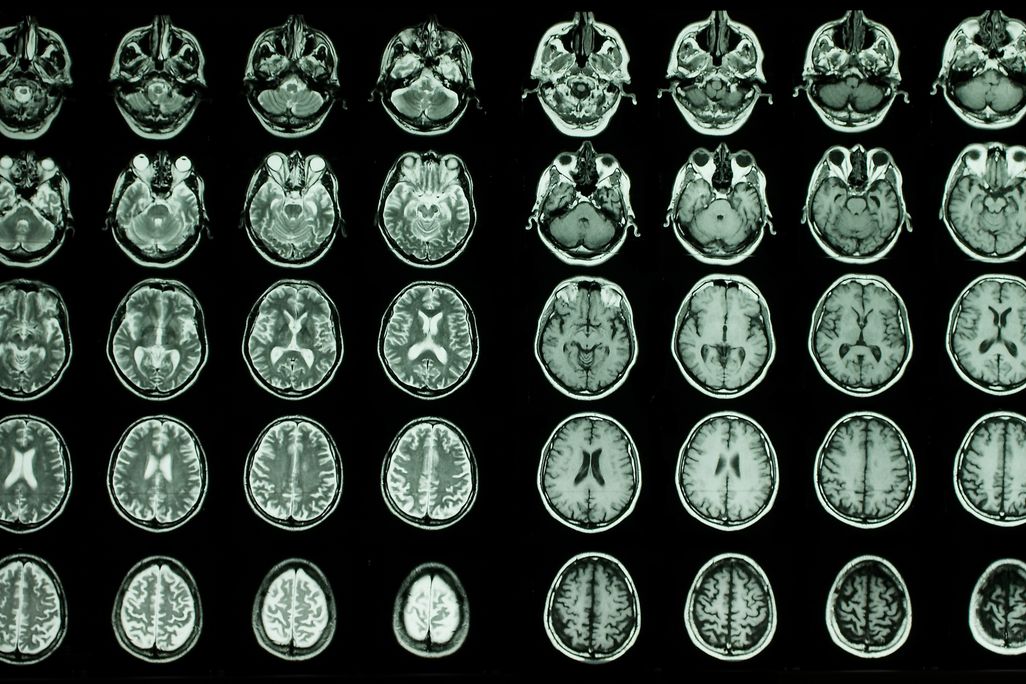

Researchers looked at brain scan data and results from blood tests to search for correlation between certain proteins and brain aging. dem10 via Getty Images

In a paper published this month in Nature Aging, a team of scientists analyzed almost 11,000 magnetic resonance imaging (MRI) brain scans from people ages 45 to 82 that were included in the U.K. Biobank. They used artificial intelligence to determine the “brain age” of the scans based on features including brain volume and surface area—essentially, they predicted how old a person is based on their brain data. This “brain age” number can be different from the chronological age of the individual and can shed light on cognitive aging and risk for neurodegenerative diseases.